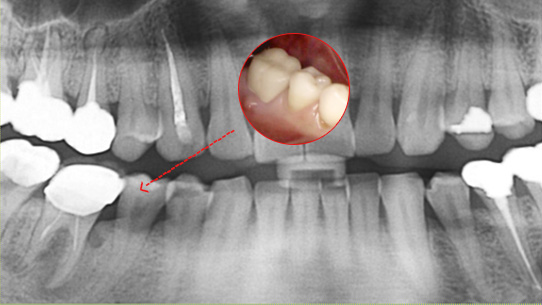

심한 염증으로 치조골이 광범위하게 소실, 아래쪽 신경관이 가까이 있어 치근단수술이 불가능한 상태, 타 병원에서 임플란트 진단을 받았지만, 고운미소치과에서 치아를 발치하고 뿌리 쪽 염증을 제거한 후 발치한 치아를 다시 심는 치아재식술을 시행하였습니다.

기존 신경치료 부위에 염증과 치조골이 소실되고 있는 상태

치아를 발치하고 염증을 제거, MTA로 충전하고

치아를 다시 심음. (난이도 중)